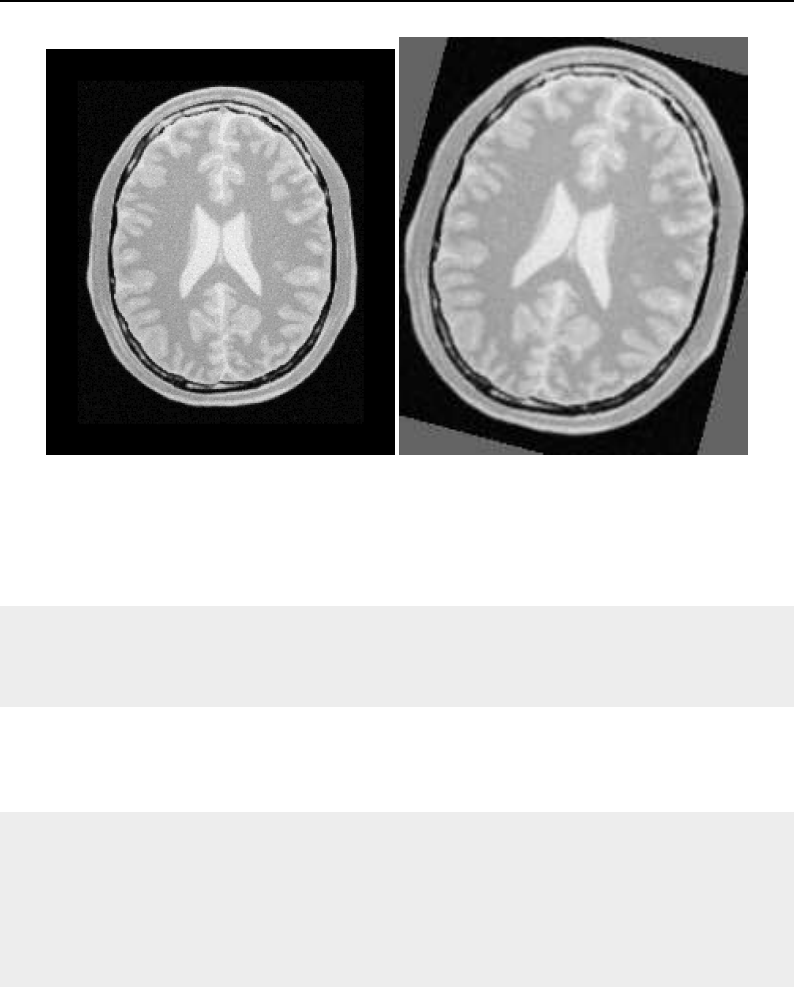

The National Library of Medicine Insight Segmentation and Registration Toolkit, shortened as the

Insight Toolkit (ITK), is an open-source software toolkit for performing registration and segmenta-

tion. Segmentation is the process of identifying and classifying data found in a digitally sampled

representation. Typically the sampled representation is an image acquired from such medical instru-

mentation as CT or MRI scanners. Registration is the task of aligning or developing correspondences

between data. For example, in the medical environment, a CT scan may be aligned with a MRI scan

in order to combine the information contained in both.